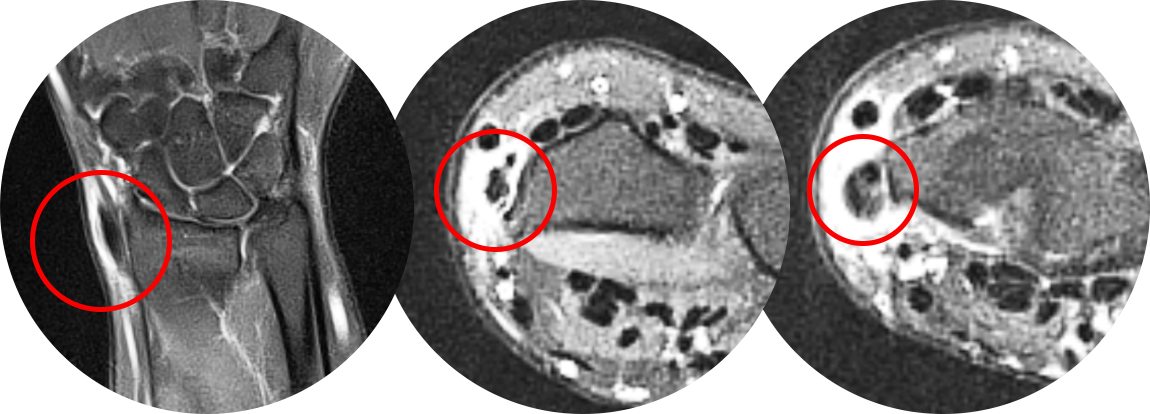

개방형 제1신전지대 유리술은 다음 그림 처럼 1.5~2cm 정도의 횡방향의 최소 절개로

다음 사진처럼 천층 요골신경 분지, 장무지외전건(APL), 단무지신건(EPB) 3가지 구조물에 대한 확인을 시행합니다.

신전지대를 유리하면서 건활액막염이 심할 경우 건활액막 절제술을 같이 시행해줄 수 있으며,

주로 비수술적인 치료가 실패한 환자에게 시행하여 높은 치료 성공률을 보이는 수술법입니다.